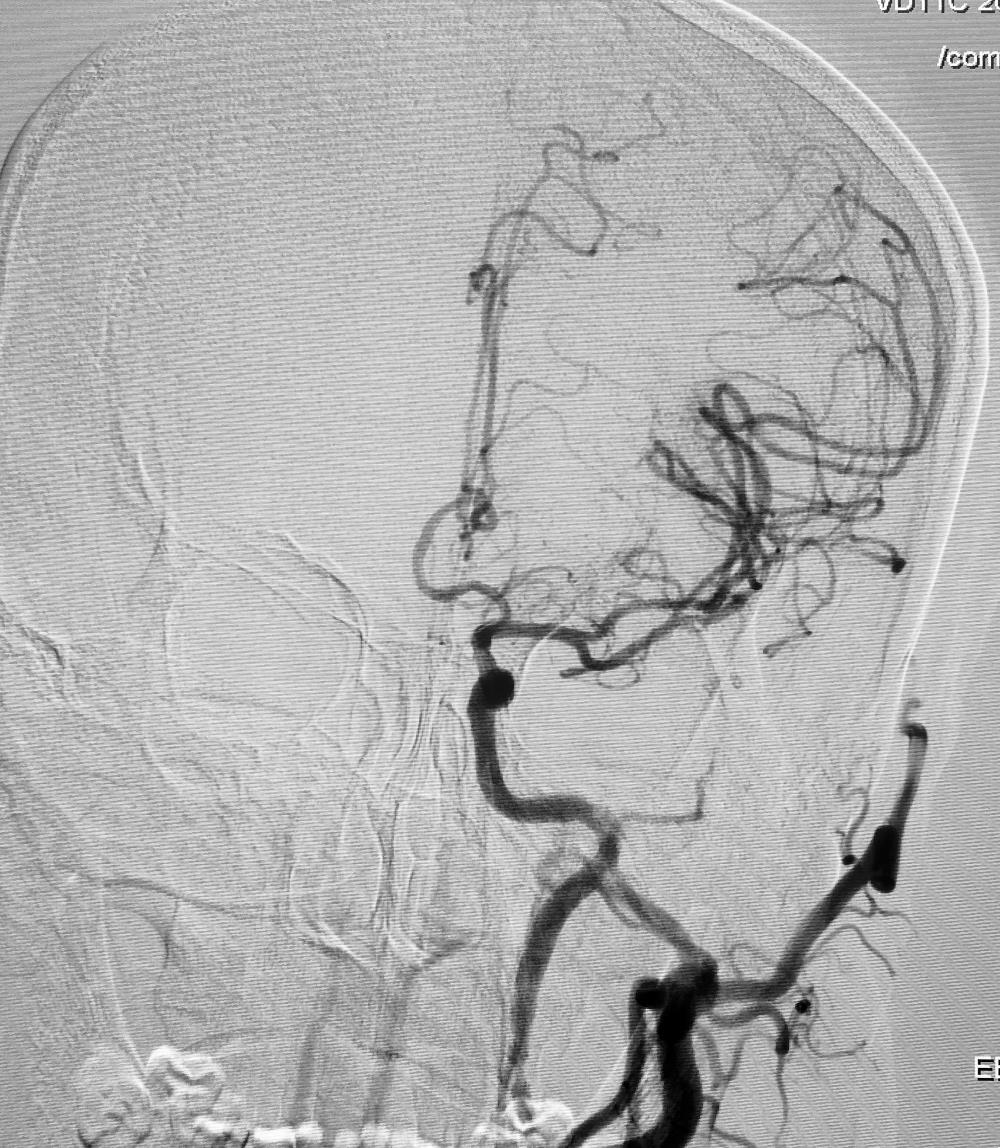

术后DSA

经过周密的术前准备,脑科医院神经介入团队在局麻下为该患者施行左侧颈内动脉闭塞开通术,术中成功植入一枚颈内动脉支架,术后即刻颈内动脉血流通畅,分支血管显影良好。

经过及时手术,患者言语不清和肢体无力等症状完全消失,未再次发作,经过精心细致的治疗,挽救了患者的生命,排除了险情,术后2周该患者顺利出院。